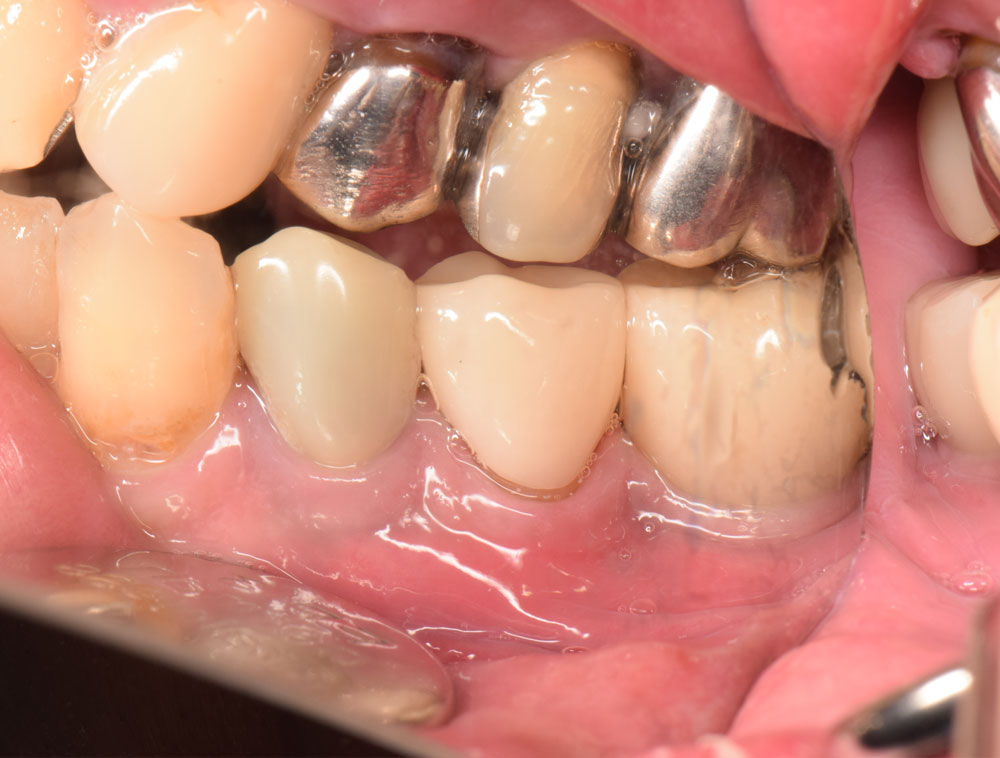

治療後

患者さんは50代の男性で、顎を動かして話したり食べたりする際、奥歯に過度の力や加わり、また上下の歯同士がぶつかることで、歯に負担がかかりその1本の歯だけでなく周囲の歯にも影響を及ぼしていました。そのため他医院で保険による銀歯の被せ物の治療を繰り返されていらっしゃったとのこです。今回は下顎の銀歯を白いセラミックで綺麗にしたいということで、恵比寿・広尾歯科に来院されました。お口のなかを拝見すると本来は顎が左右に動く際には犬歯が起点となって、奥歯に強い横向きの力が加わらないように隙間をつくるのですが、この患者さんは犬歯の働きが正しくできずに奥歯に強い力が加わり続けていました。この強い噛み合わせは歯周病の要因(咬合性外傷)となったり、周囲の歯をふくみ欠け・割れを引き起こすことがあります。根本原因を解決せずに白いセラミックで治療しても、固いセラミックにより反対側の歯を痛めてしまったり、時には固いセラミックも欠けるようなダメージを歯に受けることもあります。そこで根本的な噛み合わせと顎運動の改善から治療をスタートし、仮歯で時間をかけて患者さんの理想的な犬歯誘導が行われる形態と噛み合わせをつくり、最終的にセラミックの本歯で治療を終えました。

最後にセラミックによる本歯で数日間お過ごし頂いたあと、再度ご来院頂いて最終的な噛み合わせの調整をおこないます。これは同じ歯冠外形でも材質の異なるセラミックの本歯に置き換わることで、周囲や反対の歯との噛み合わせがマイクロ単位で変化するためです。この最終的な咬合調整を怠ると、さまざまなトラブルの原因となります。恵比寿・広尾歯科では見た目の治療だけでなく話す、噛む、飲み込むという歯とお口の機能回復をもっとも大切に考えています。